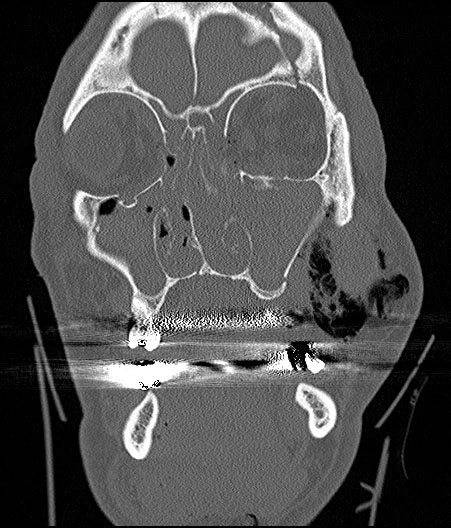

The diagnosis of TON is primarily clinical. There are some tests that can aid in the management and diagnosis of TON. It is important to obtain neuroimaging, usually a CT of the orbit with coronal and axial thin sections (1 mm) through the optic canal are crucial to visualize the optic nerve as well as the optic canal and evaluate for fracture. This can help assess for compression of the optic nerve by a hematoma or bony fragments impinging on the optic nerve, which could provide an indication for urgent surgical intervention. Automated visual field testing such as a Humphrey (HVF) can be used to characterize visual field defects/scotomas in patients with TON, if acuity remains adequate for such testing. Finally, a visual evoked potential (VEP) can be used to characterize the electrical activity of the optic nerve.

Beyond optic nerve assessment, a CT can also evaluate the adjacent sphenoid-ethmoidal sinuses, while computed tomographic angiography (CTA) proves helpful in assessing the internal carotid artery (ICA). This comprehensive approach is essential for surgical planning and can aid in diagnosing concomitant craniomaxillofacial injuries. [9] [10] [11] Patients with TON can also have other traumatic complications, such as carotid-cavernous fistula and carotid pseudoaneurysm, which should be considered during the evaluation. CTA is recommended for identifying these complications. [12][13][14] This multifaceted diagnostic approach ensures a thorough evaluation and appropriate management of TON and associated injuries.[8]